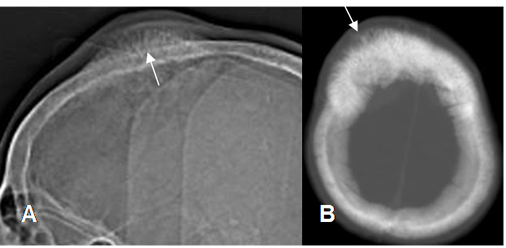

Fig 70 A. Osteosarcoma.

A: Rx lateral. Reacción perióstica en sol naciente, con prominencia de tejidos blandos.

B: TAC axial. Calcificación osteoide de la matriz, con reacción perióstica en sol naciente.